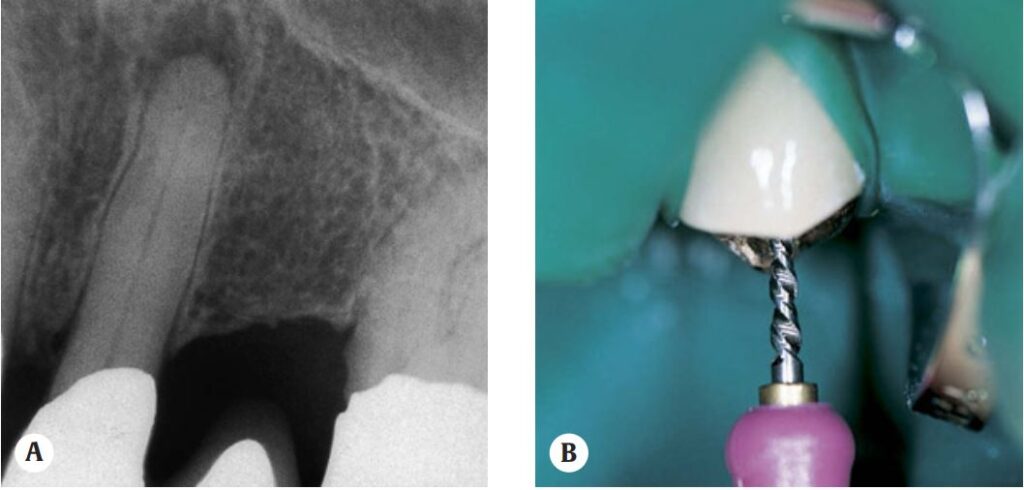

Trước khi bắt đầu sửa soạn phải xác định độ thông suốt ống tủy bằng trâm nhỏ #15 (hoặc nhỏ hơn nếu cần).

Sau đó sử dụng mũi Gates-Glidden số 1 (tương ứng trâm #50) để mở rộng ống tủy phía trên cho đến tận đoạn ống tủy cong, đầu mũi được bôi chất bôi trơn. Mũi Gates số 2 (trâm #70) được sử dụng tiếp theo tương tự nhưng ngắn hơn 1 mm. Các mũi Gates số 3, 4, 5 được sử dụng lần lượt và mỗi mũi thì lại ngắn hơn 1 mm. Sau mỗi lần rút ra phải bơm rửa ống tủy nhiều với NaOCl.

Sau khi sửa soạn phần trên ống tủy thì chụp phim xác định chiều dài làm việc bằng file K #15. Nếu ống tủy quá hẹp không đưa được file K 15 thì dùng file H để mở rộng ra, sau đó dùng file K số nhỏ uốn cong đầu trâm để đi hết chiều dài làm việc. Tiếp tục sửa soạn tăng lên đến số lớn hơn, 35 hoặc 40.

Ca lâm sàng